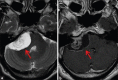

Schwannomas are benign soft-tissue tumors that arise from peripheral nerve sheaths throughout the body and are commonly encountered in patients with neurofibromatosis Type 2. The vast majority of schwannomas are benign, with rare cases of malignant transformation reported. In this pictorial review, we discuss the magnetic resonance imaging (MRI) appearance of schwannomas by demonstrating a collection of tumors from different parts of the body that exhibit similar MRI characteristics. We review strategies to distinguish schwannomas from malignant soft-tissue tumors while exploring the anatomic and histologic origins of these tumors to discuss how this correlates with their imaging findings. Familiarity with the MRI appearance of schwannomas can help aid in the differential diagnosis of soft-tissue masses, especially in unexpected locations.